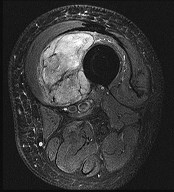

Question 4:

A 32-year-old female presents with progressive knee pain. Imaging reveals an eccentric, lytic epiphyseal-metaphyseal lesion of the distal femur. A biopsy demonstrates multinucleated giant cells in a background of mononuclear stromal cells. If neoadjuvant medical therapy is utilized prior to curettage, the mechanism of action of the most appropriate drug is:

Explanation:

The diagnosis is Giant Cell Tumor (GCT) of bone. Denosumab is a monoclonal antibody often used in the medical management of GCT. Its mechanism of action is the inhibition of RANK ligand (RANKL). In GCT, the neoplastic cells are the mononuclear stromal cells, which express RANKL. This recruits and activates the non-neoplastic, multinucleated osteoclast-like giant cells that cause the massive bone resorption.